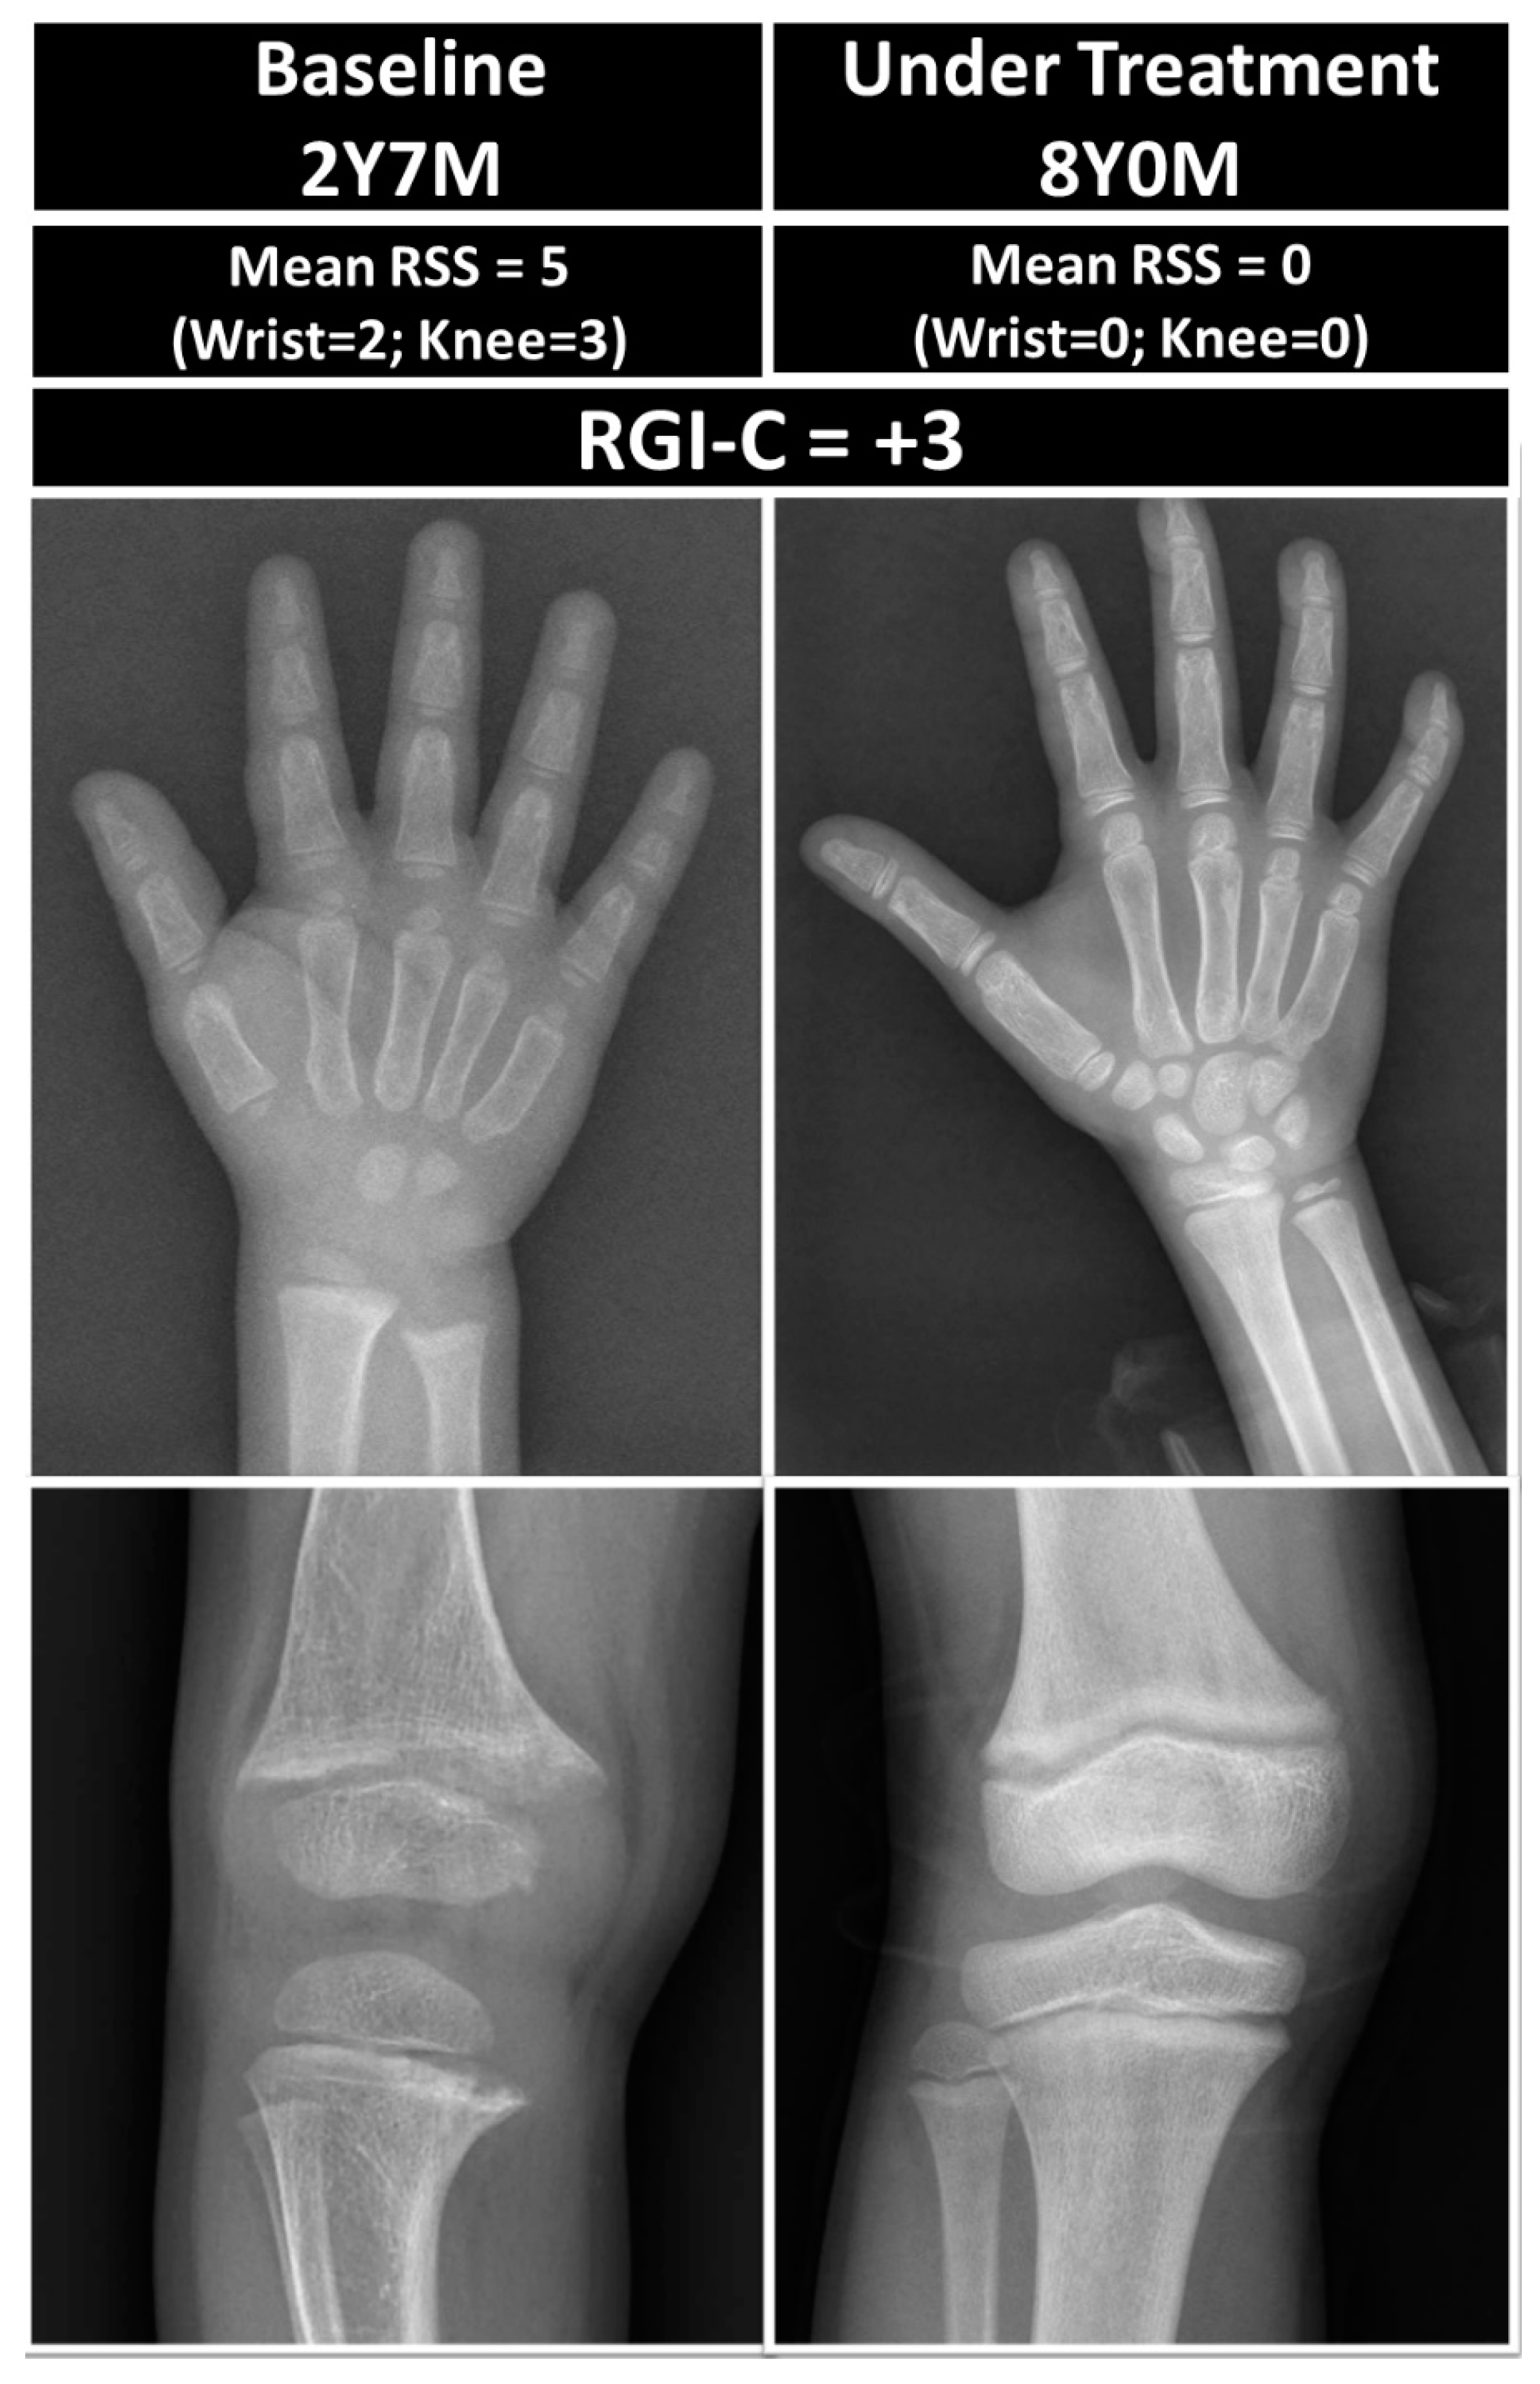

2.3.4. Radiographic Grades and Healing